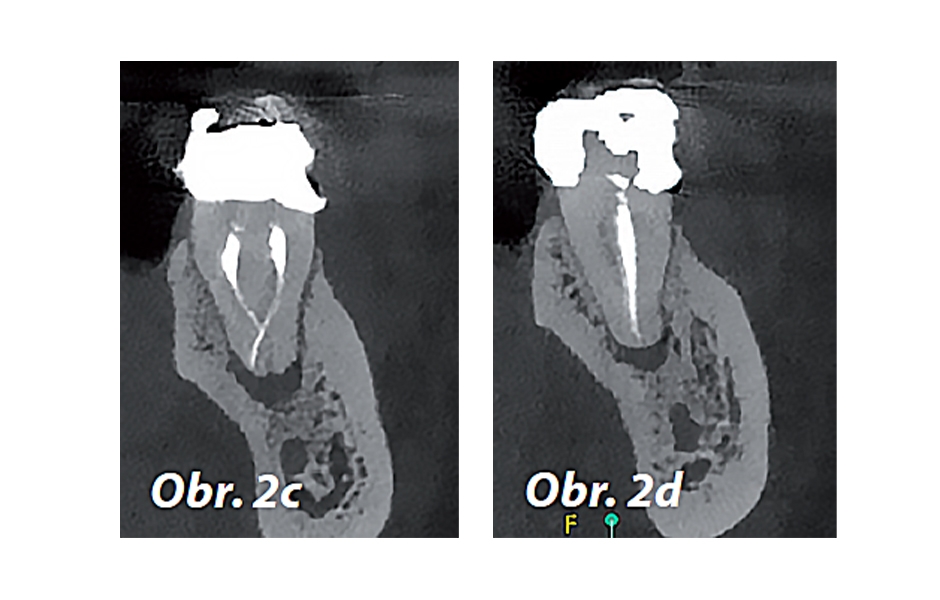

Pro radiologickou diagnostiku byl pořízen periapikální (PA) rentgenový snímek (obr. 1) a CBCT snímek s omezeným zorným polem (obr. 2a–d). Předchozí endodontické ošetření zahrnovalo zaplnění tří kanálků s nedostatečnou hustotou výplně v apikální třetině meziálních a distálních kořenů. V oblasti apexů meziálních (3 × 3 mm) a distálních (3 × 5 mm) kořenů byla patrná periapikální projasnění. CBCT (obr. 2a–d) potvrdilo nezaplněný distolingvální (DL) kanálek a možný střední meziální (MM) kanálek; koronální CBCT řez meziálního kořene (obr. 2c) také naznačuje přítomnost apikální delty spíše než jediného apikálního foramenu. Nebyly zjištěny žádné známky prasklin či fraktur.

Obr. 2c, d: Předoperační CBCT řezy zubu 46 – c) meziální kořen, d) distální kořen.